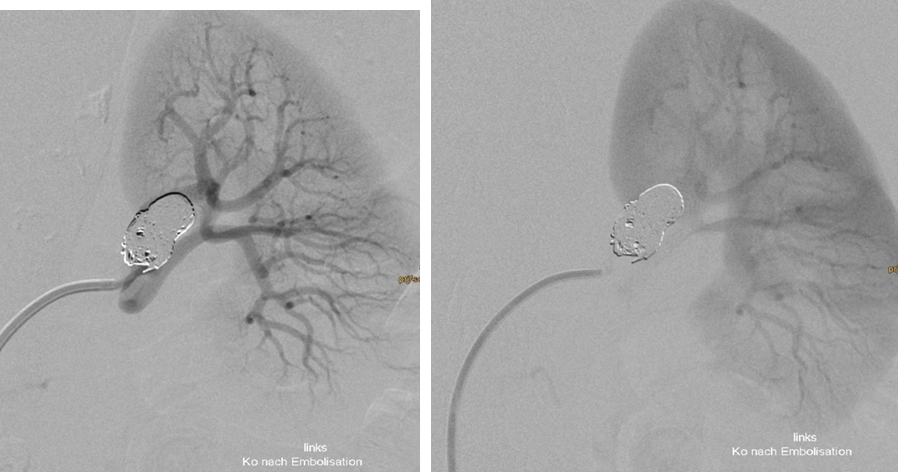

Treatment of complex aneurysms: Treatment of complex intracranial aneurysms often involves balloon-remodeling, stent-assisted coiling, or flow diverters. These methods can also be used for non-neurovascular procedures, specifically in treatment of visceral aneurysms. Renal artery aneurysms are most frequently located in the renal hilum, where the main renal artery diverts into its ventral and dorsal branch. Preservation of all renal artery branches may request advanced techniques as mentioned above (1); Fig 1,2.

Fig. 1: Balloon assisted embolisation of a broad based renal artery aneurysm

Fig. 2: Double balloon assisted embolisation in dual catheter technique was applied

Fig. 3: Successful exclusion of the aneurysm with preservation of both renal artery branches